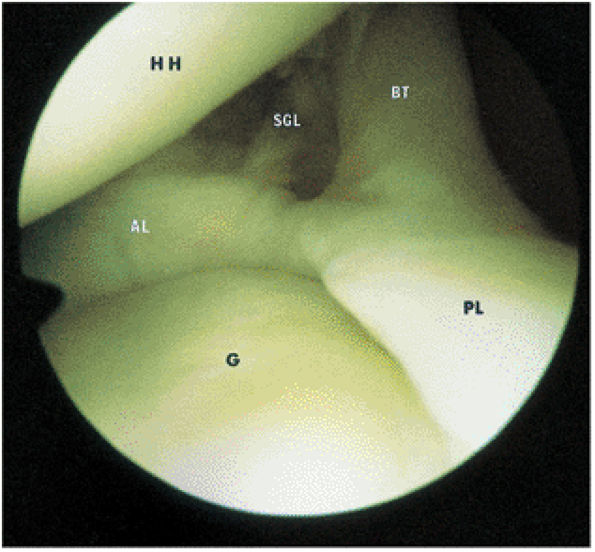

FIGURE 8.68 ● The biceps tendon (BT) contributes to the superior anterior labrum (AL) and the superior posterior labrum (PL) in the BLC. One component of the LHBT attaches to the supraglenoid tubercle. Extra-articular fibers attach to the lateral edge of the base of the coracoid process. The intra-articular portion of the LHBT is oriented at an approximate right angle to the surface of the glenoid (G). HH, humeral head; SGL, superior glenohumeral ligament.

|